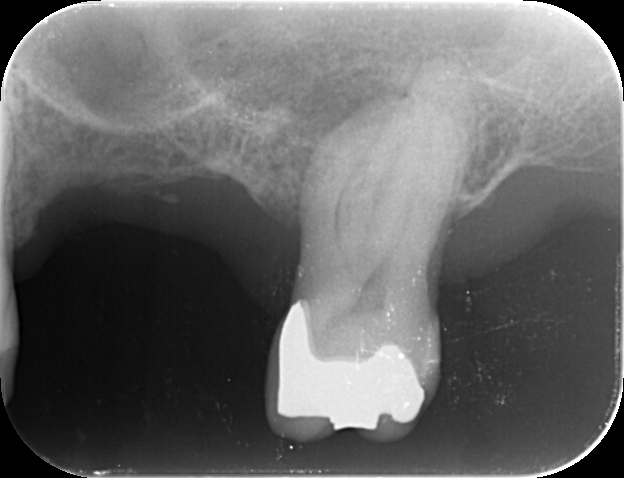

下の写真の歯の中にある黒い筋が「根管」です。

根管の形状は患者さんごとに異なり、非常に複雑です。さらに、狭い部分は直径1mmもありません。狭くて複雑な根管から、神経組織を取り除く治療がいかに難しいか、おわかりいただけると思います。

しかし、多くの歯科医院では、患部を「肉眼」で見ながらこの治療を行っています。これではどうしても限界があります。

当院では、「マイクロスコープ」や「高倍率ルーペ」を用いて、拡大視野のもと治療を行います。マイクロスコープでは、患部を最大で数十倍に拡大して見られるので、精度の高い治療が可能になります。また、当院ではマイクロスコープでの映像を動画に残し、患者さんに確認してもらうこともできます。